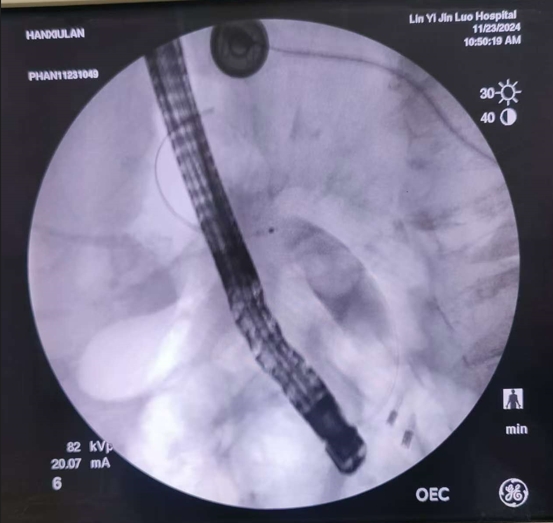

昨日在全程的精心監(jiān)護(hù)下,為了做到更安全、萬無一失,姜開通主任還邀請了市醫(yī)院的曾憲忠主任共同參與,為老人實(shí)施了內(nèi)鏡下的逆行膽管造影治療術(shù),病人年齡超高,出現(xiàn)乳頭處憩室,遇到困難,兩位主任憑多年經(jīng)驗(yàn)及超高手法,較為順利給予病人做了微創(chuàng)治療,術(shù)后老人的生命體征非常平穩(wěn),沒有任何不適,今日查房患者和家屬都感到非常滿意和感激。